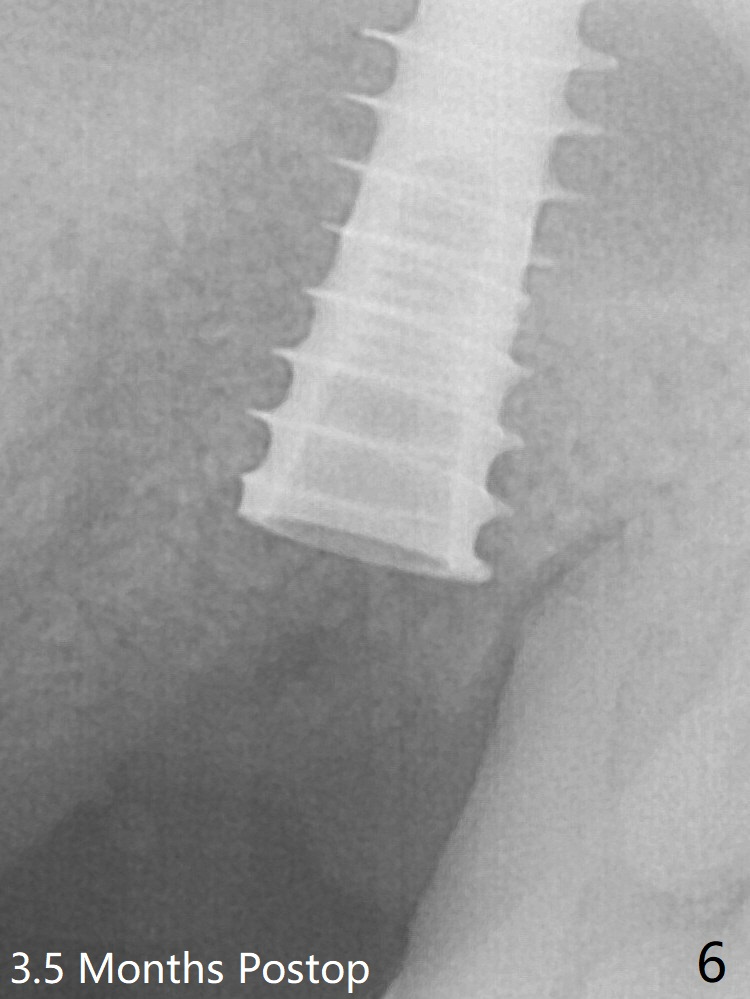

More of allograft (Fig.3 *) is placed prior to placement of 5x11 mm IBS implant (~30 Ncm). The latter is placed palatal. Last the allograft is placed palatal. A 5x4(2) mm abutment is placed to hold periodontal dressing in place. When the ridge is narrow, the implant should be small; 4 mm probably the most appropriate in this case. The implant seems to be osteotointegrated 3.5 months posotp (Fig.6).